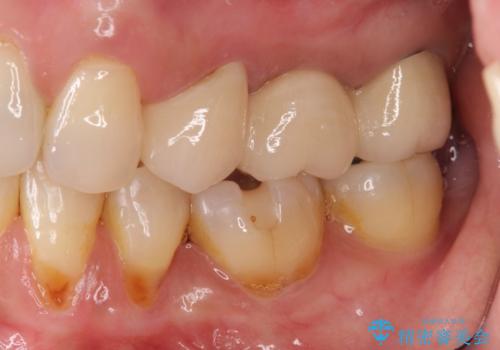

歯ぐきのボリュームが保たれることで、清掃性の高いブリッジ治療を行うことが可能になります。

自然な仕上がりのブリッジ治療を達成することができ満足いただくことができました。